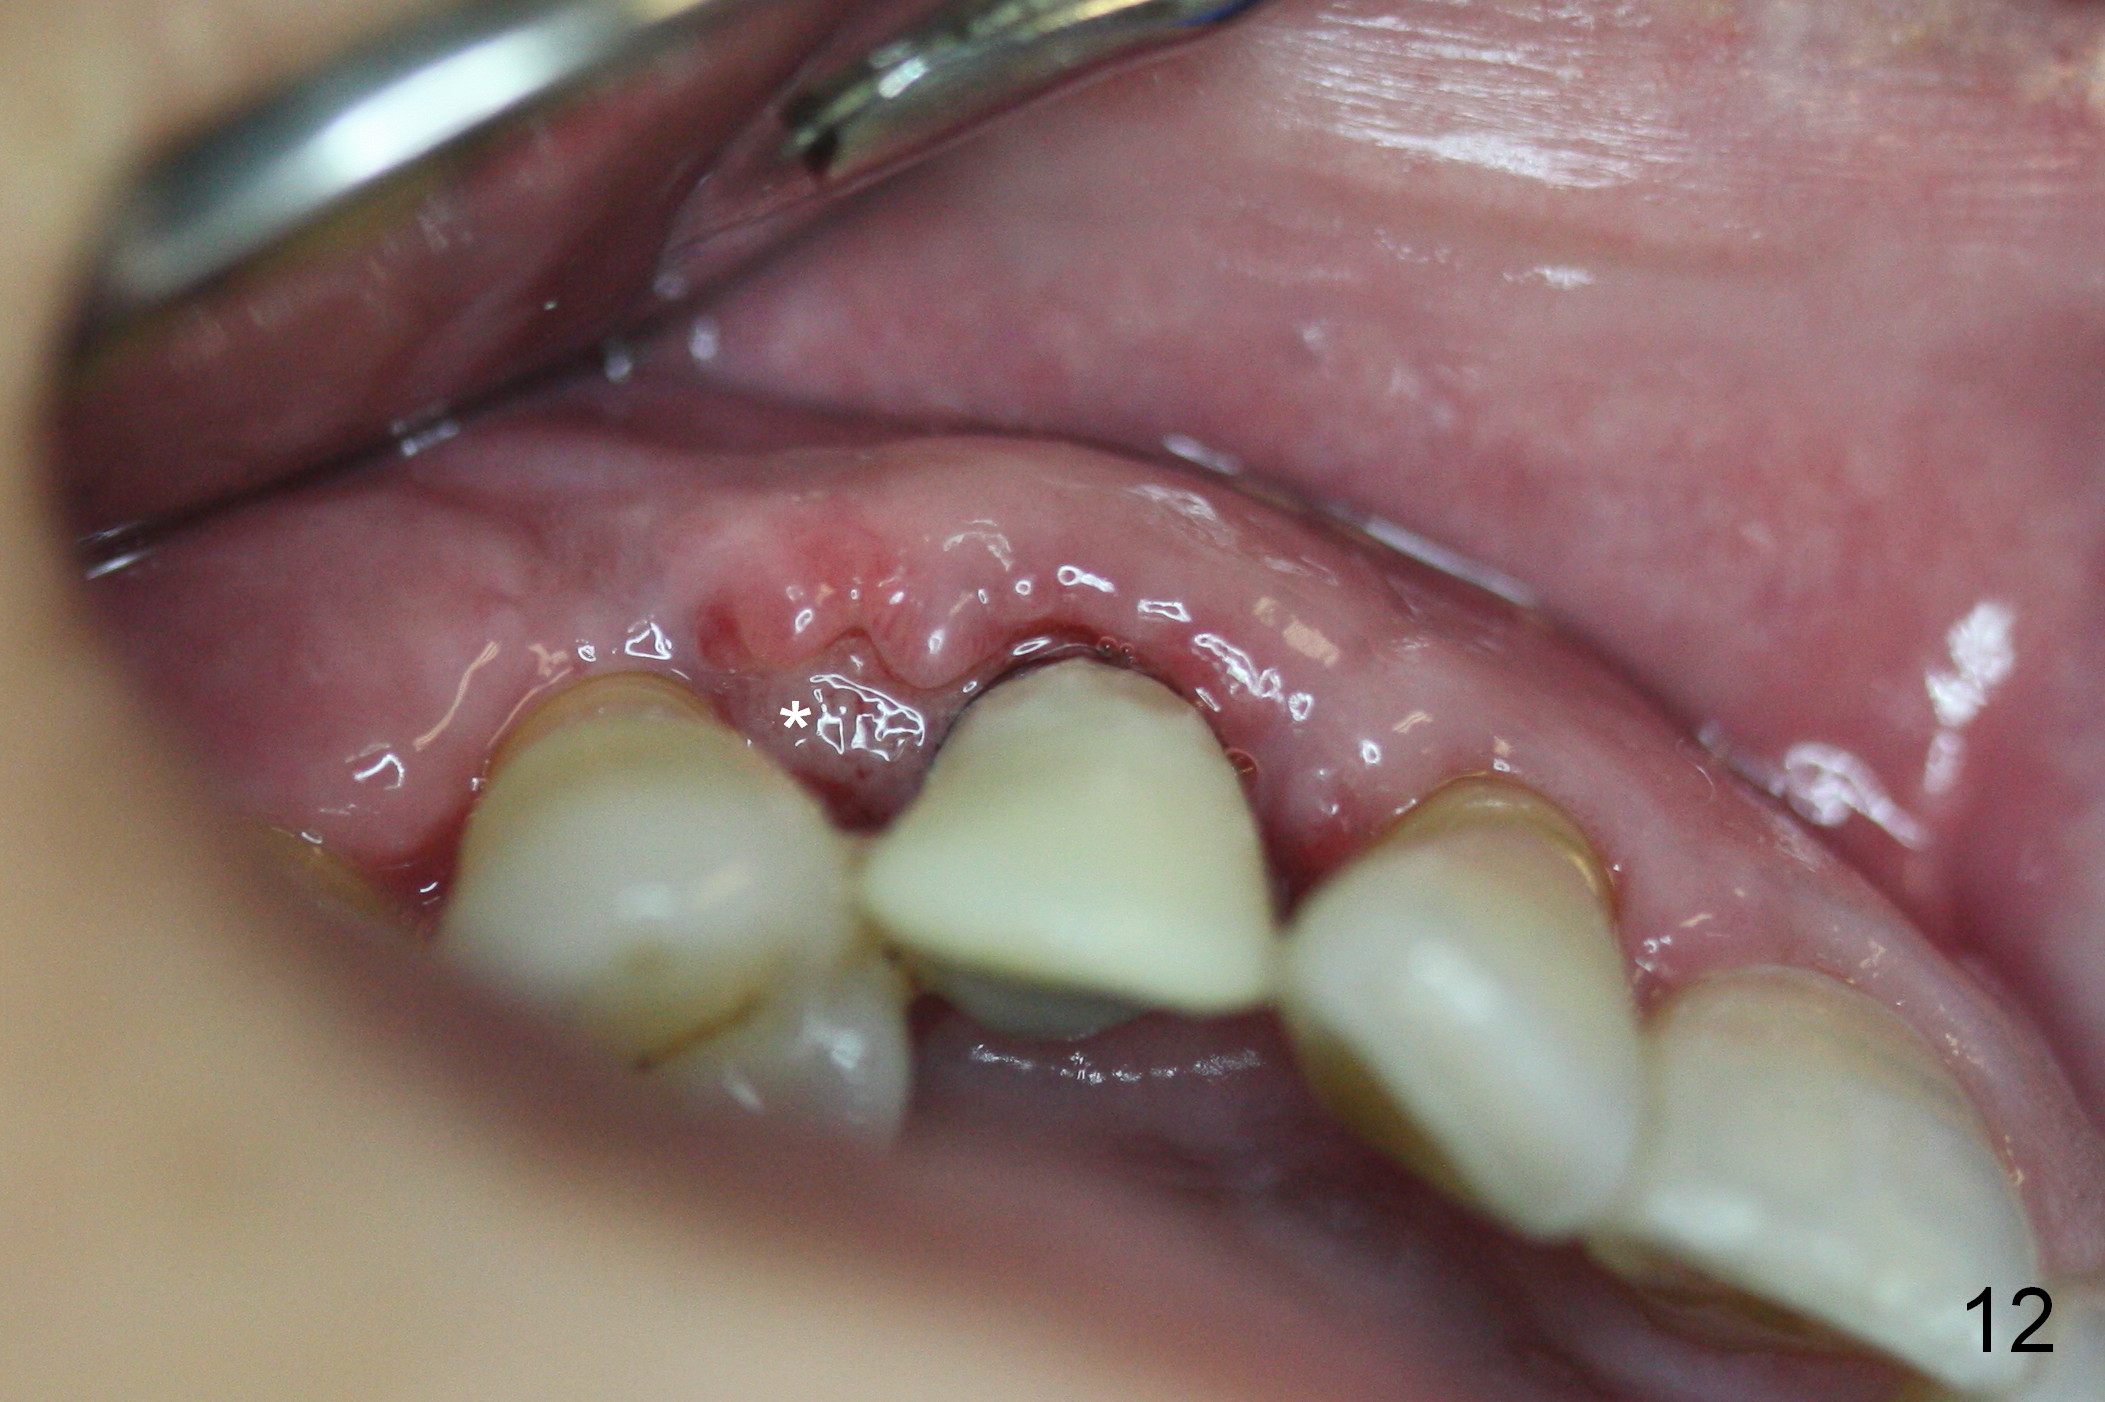

The patient complains of bad smell from the operative field 7 days postop. The wound is gapping with pseudo membrane, which is re-epithelized 14 days postop (Fig.11,12 *) with disappearance of the bad smell.